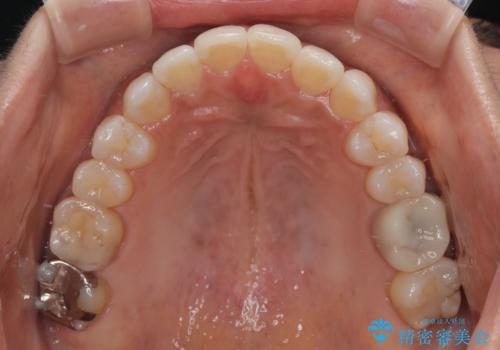

クロスバイトを治したい インビザラインによる矯正治療

- 前歯のクロスバイトを気にして来院された患者様です。

上下ともに、前歯部を中心にやや叢生が認められる程度であったため、ワイヤーでもインビザラインでも、どちらでも対応可能な状態でした。

咬合力が非常に強く、治療が進むにつれて上下奥歯が離開してくることが予想されるため、治療途中から上下の顎間ゴムを使用することを理解いただき、インビザラインによる矯正治療を行うこととしました。